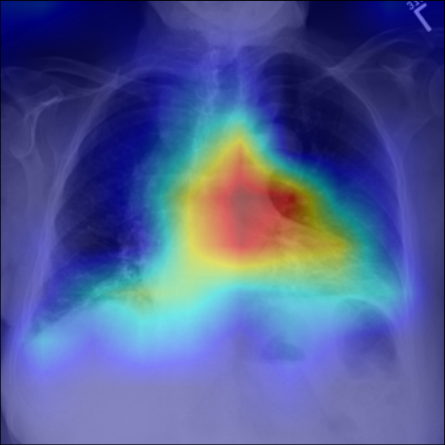

Refer to caption

Figure 5: Visualization of attention map in PLAN on MS-CXR. The red boxes indicate the corresponding ground truth of grounding. Highlighted pixels represent higher activation weights correlating specific words with regions in the image.

IV-B1 Phrase Grounding

Phrase grounding associates textual phrases (e.g., disease descriptions or anatomical terms) with corresponding regions in medical images, offering precise diagnostic insights and enhancing model interpretability. Table II presents the phrase grounding results on the MS-CXR dataset. Using the Contrast-to-Noise Ratio (CNR) [27] as the evaluation metric, PLAN achieved the highest CNR across eight disease categories, outperforming MGCA and PRIOR. Heatmaps generated with Grad-CAM (Figure 4) further illustrate PLAN’s ability to accurately localize lesion sites and align disease-related phrases with image regions. Additional comparisons with baseline methods can be found in Figure 5. These findings highlight PLAN’s superior precision and interpretability in phrase grounding tasks.